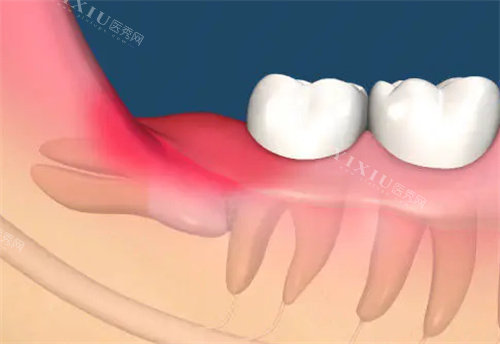

等了没一会儿,就轮到我见孙医生了。他看起来特别可靠,说话也很温和,详细问了我智齿发炎的情况,还仔细检查了口腔。他一边看一边给我解释,说我的两颗智齿都是横着长的,顶到了前面的牙齿,不仅容易发炎,时间长了还会把前面的牙顶坏,所以建议尽快拔掉。我当时就问:“拔牙会不会特别疼啊?” 孙医生笑着说:“放心,我们会用适合的麻醉方式,整个过程你不会有明显痛感,术后也会详细告诉你注意事项,帮你顺利改善。” 听他这么一说,我心里踏实多了。

确定好拔牙方案后,护士小姐姐先带我去拍了牙片,然后就开始做术前准备。打麻醉的时候,我紧张得手心冒汗,护士小姐姐一直轻声安慰我,分散我的注意力。没想到麻醉针打进去比想象中轻松多了,就像被蚊子叮了一下,稍微有点刺痛,很快就没感觉了。

拔牙过程真的超顺利!孙医生手法特别娴熟,我能感觉到他在操作,但一点都不疼,只听到一些轻微的声音。大概十几分钟,智齿就拔下来了,接着很快第二颗也搞定了。拔完后,孙医生把拔下来的智齿拿给我看,还耐心讲解为什么这两颗牙必须拔。护士小姐姐马上给我咬上止血棉,又反复叮嘱我术后注意事项,比如咬住棉花半小时后才能吐掉、24 小时内不能刷牙漱口、饮食要清淡等等,说得特别详细。